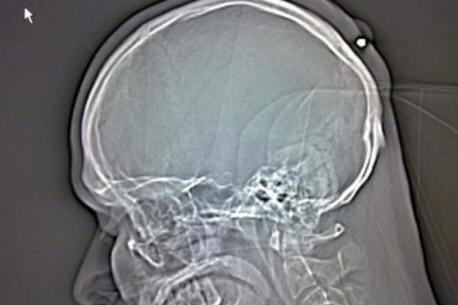

Kad je govorio o bolnici, Autullo je to odbio vjerovati doktori su mu pokazali: na rendgenu je bilo jasno da to željezni nokat od osam centimetara zabio se točno u lubanju kutije Dantea. Prije nego što je Hitna pomoć odvela Autullo na drugu kliniku operacije, Dante je objavio fotografiju toga na svojoj Facebook stranici rendgenska slika.